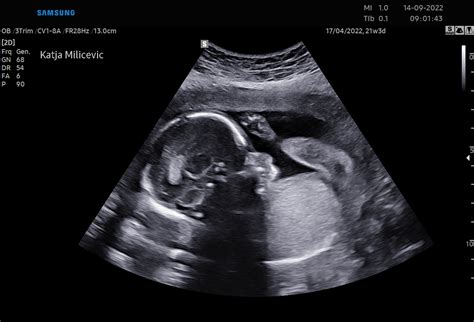

V obdobju od 3. do 8. tedna nosečnosti poteka intenziven razvoj zarodka. V tem času sta zdrav življenjski slog in izogibanje škodljivim vplivom (kot so sevanje, določena zdravila, kemikalije, okužbe, povišana telesna temperatura) še posebej pomembna. V 5. tednu se že oblikuje srček, ki začne utripati in ga je mogoče videti z ultrazvočno preiskavo. Zarodek je takrat velikosti sezamovega zrna. V 6. tednu zarodek meri štiri do šest milimetrov, njegovo srce že bije, hrbtenični kanal se zapre, oblikujejo se jetra, čeljusti, nos in mehko nebo. Zasnove za roke in noge se razvijajo v prstke.